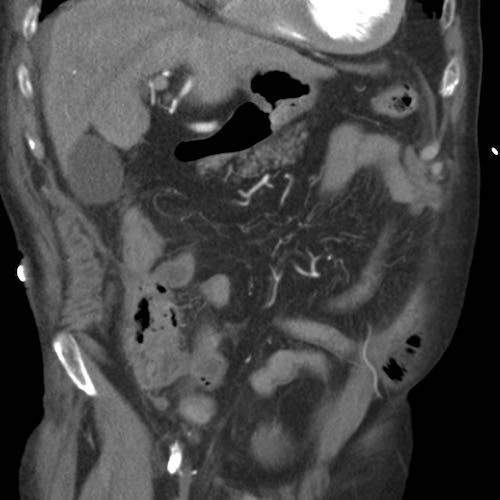

Bệnh nhân nữ 59 tuổi với cơn đau thượng vị không điển hình kéo dài hai ngày.

Siêu âm phát hiện dày thành đáng kể vùng hang vị trước môn vị, trong đó có cấu trúc tăng âm, dạng cong (đầu mũi tên), nghi ngờ xương cá.

CT xác nhận chẩn đoán.

Lưu ý rằng xương cá (mũi tên) có thể dễ dàng bị bỏ sót nếu chỉ xem trên mặt phẳng cắt coronal của CT.

Bệnh nhân hồi phục tốt sau khi lấy dị vật qua nội soi.